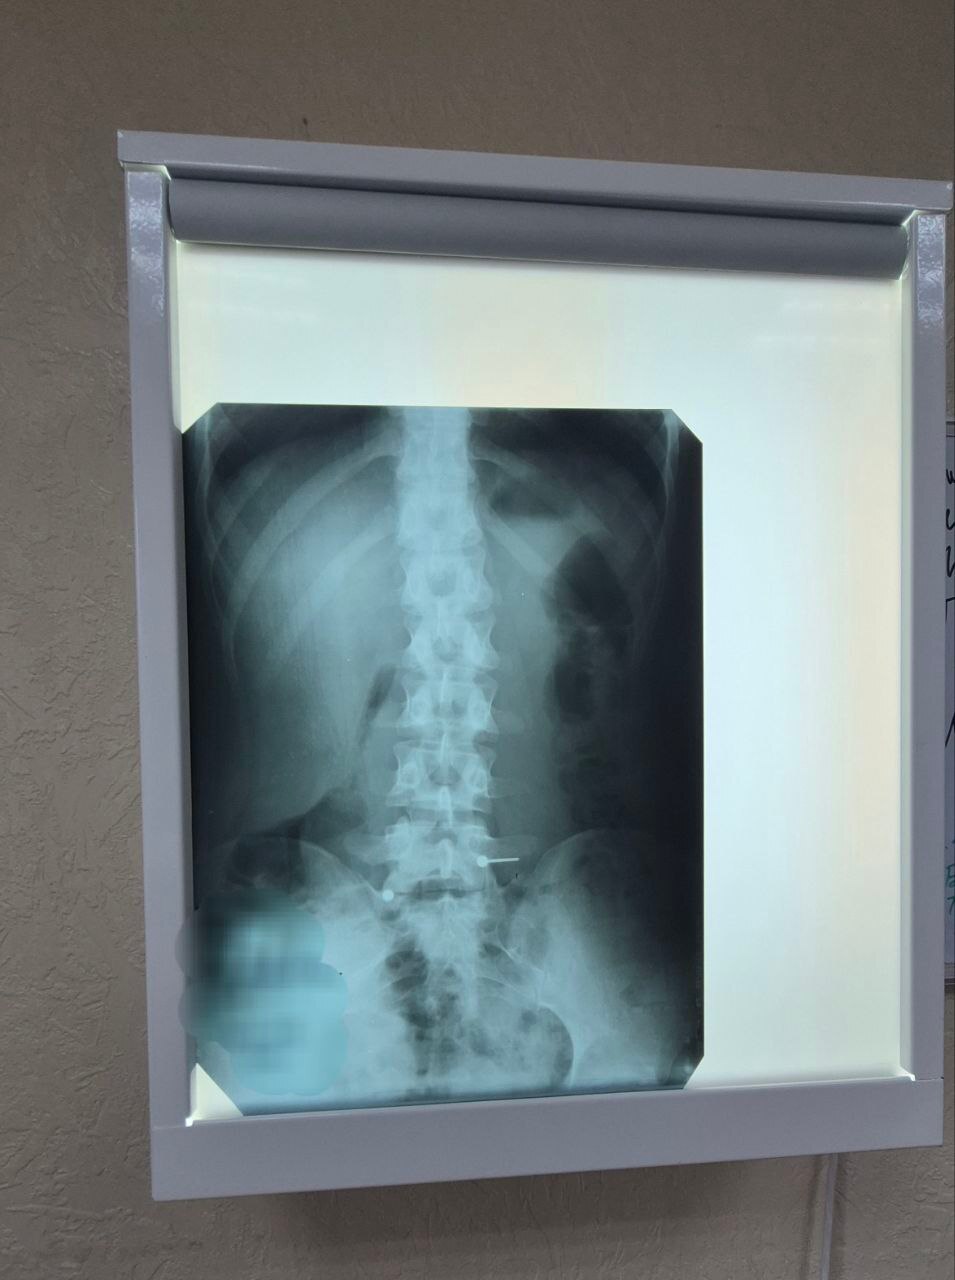

Второй пациент — 2-летний малыш. По словам мамы, за час до приезда в больницу он проглотил саморез. Точные обстоятельства выяснить не удалось, но рентген подтвердил: в организме ребенка находится острый металлический предмет. Врачи срочно провели эндоскопическую операцию и обнаружили саморез уже на входе в двенадцатиперстную кишку. Он был направлен шляпкой вниз, поэтому не повредил слизистую. Медикам удалось аккуратно извлечь его из желудка, избежав операции. Теперь саморез "украшает" коллекцию врачей-эндоскопистов больницы .